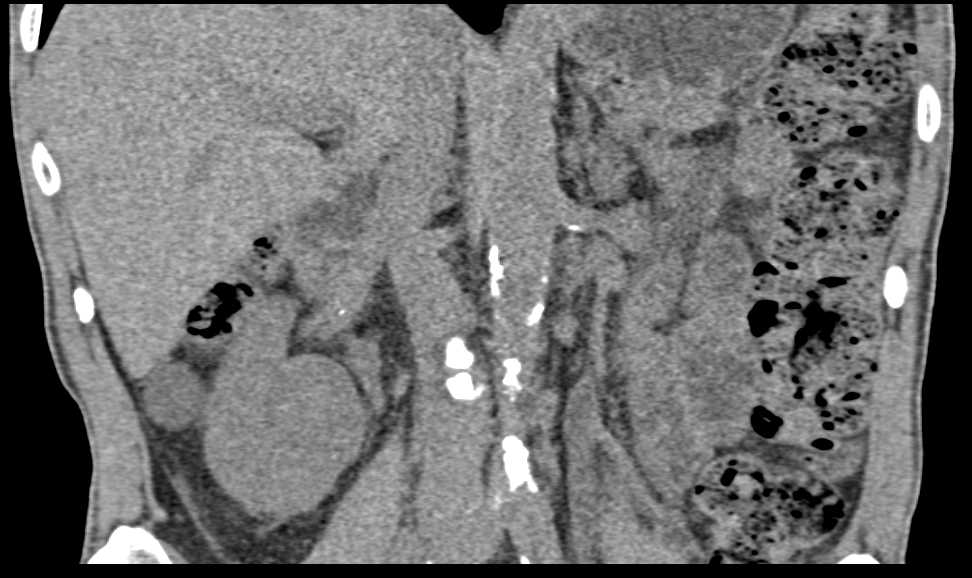

Infiltrating Carcinoma of the Left Wall of the Bladder